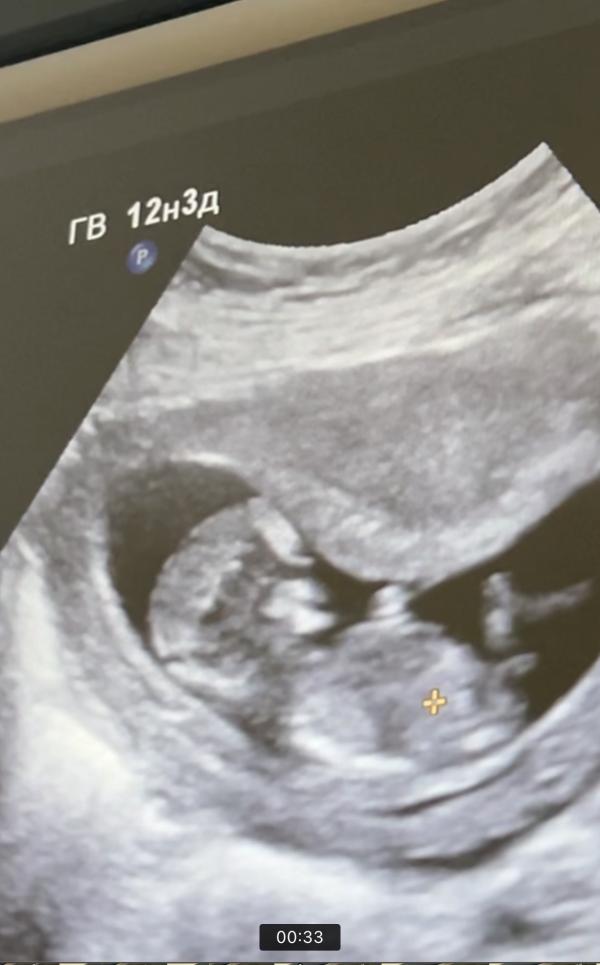

Девочки, ради интереса. Мальчик или девочка по половому бугорку? 😅 что видите

В общем, больше 30 градусов говорят, что мальчик, меньше - девочка. Это я просто ищу все признаки в надежде, что девочка у меня 😂

Писюн ещё не сформирован) у них на этом сроке одинаковый бугорок, только могут предположить по его расположению😁